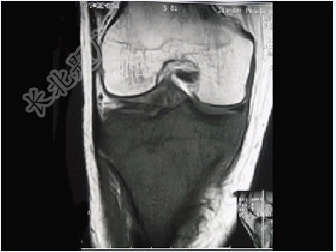

- 单项选择题患者女,28岁,右膝跌伤伴疼痛9年,加重及活动障碍1年半,经药物治疗及理疗后病情无好转,既往无特殊病史,查体跛行步态,触痛,请结合所提供的图像,选择最佳选项( )

A、骨巨细胞瘤

B、结核

C、骨肉瘤

D、滑膜肉瘤

E、软骨肉瘤